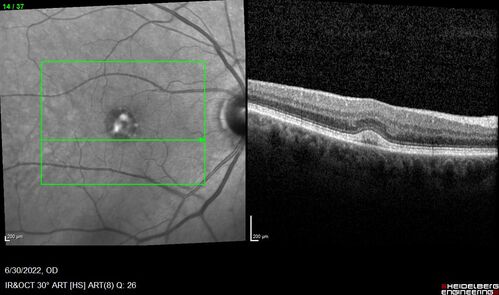

Pattern Dystrophy with Collapsed Vitelliform

74 year old female with vision loss in eye with collapsed vitelliform lesion.

Collapsed Vitelliform Pattern Dystrophy